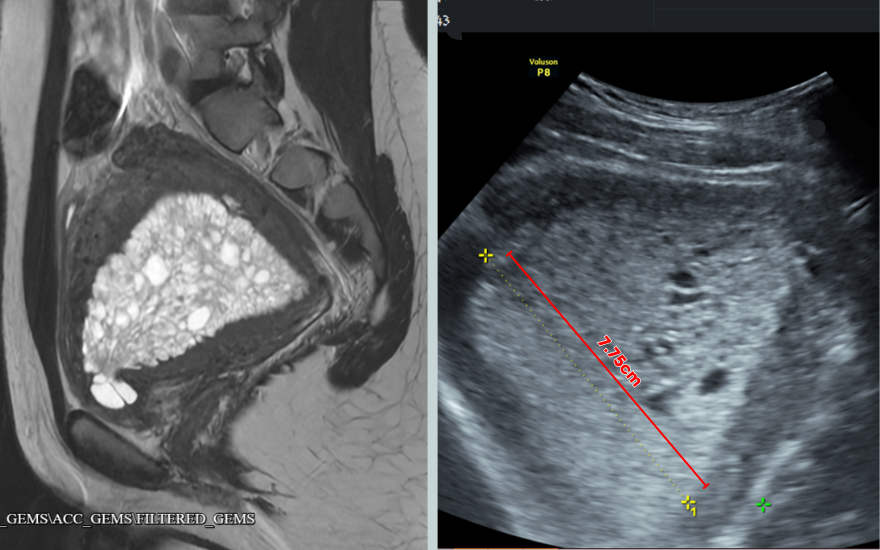

Tại Bệnh viện Đa khoa Hồng Ngọc, thông qua siêu âm, các bác sĩ nhận thấy niêm mạc tử cung của T.A dày đến 7,7cm, gấp 7 lần độ dày thông thường (tử cung của người khỏe mạnh trong những ngày rụng trứng chỉ khoảng 10-12mm).

Niêm mạc tử cung tăng sinh bất thường, dày 7.75cm.